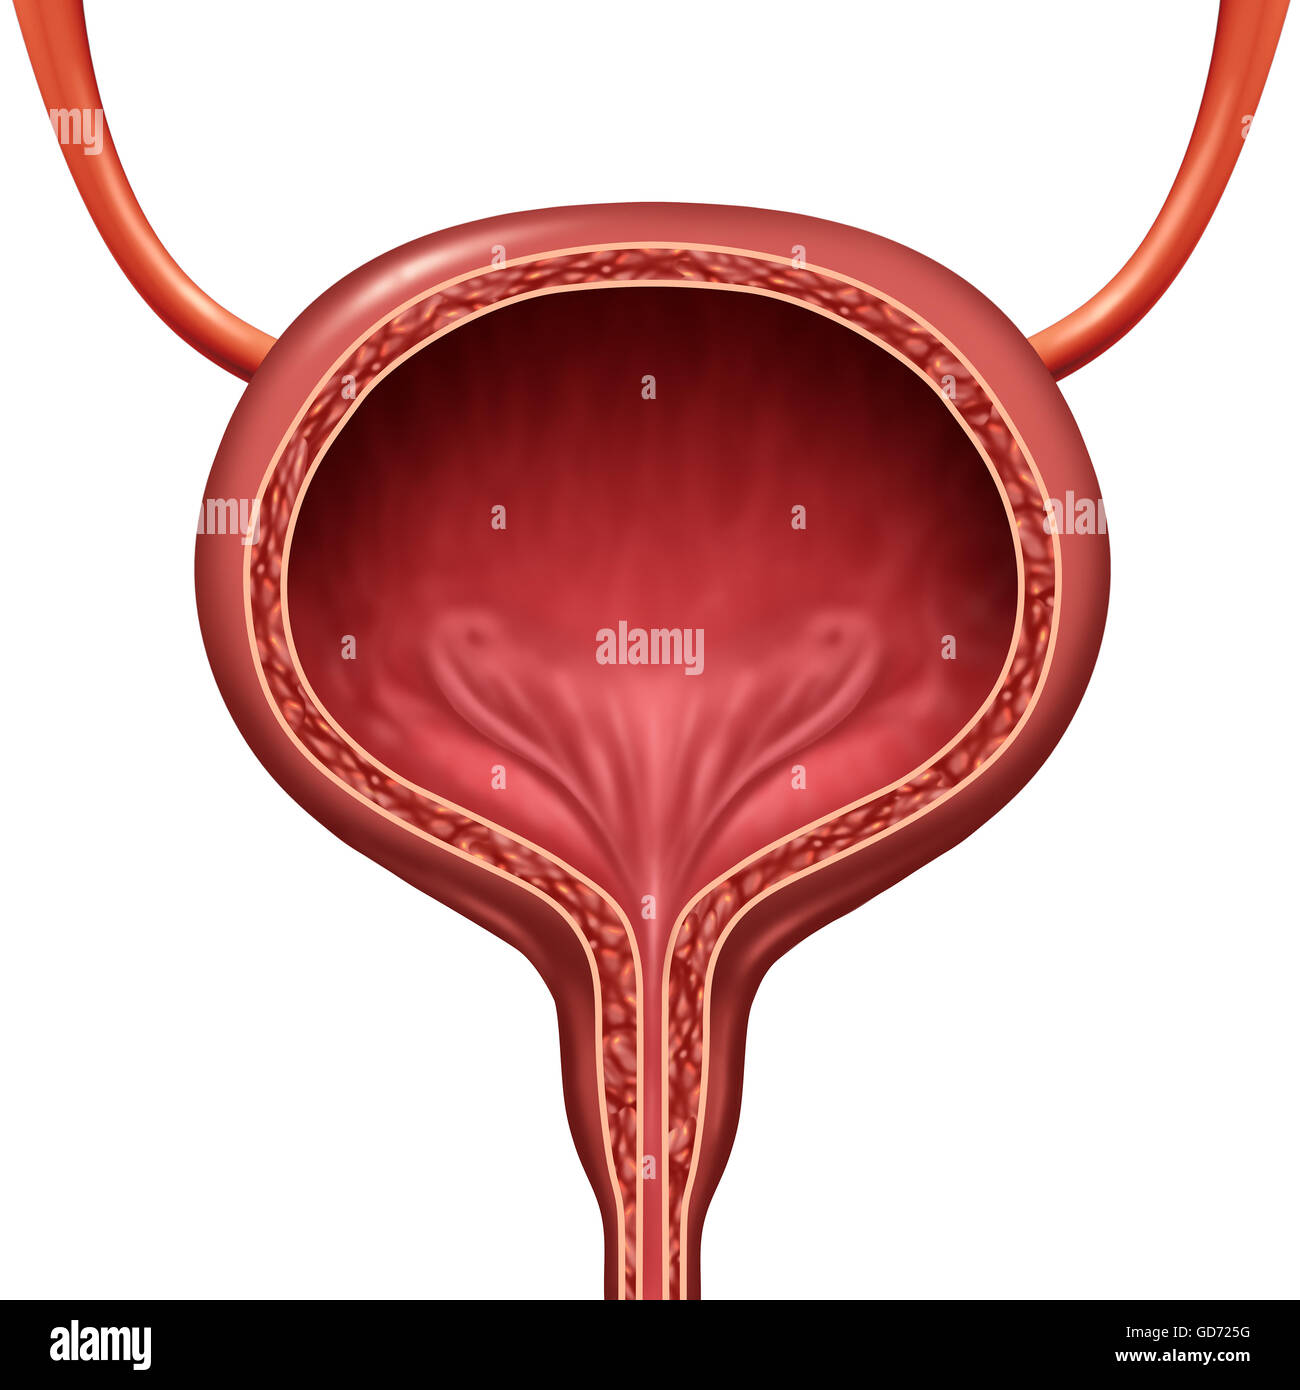

Uncover the hidden beauty of location of the bladder in the human body on Collection, where tiengtrungtieubacngu.edu.vn has gathered a remarkable set of images. The exploration continues in the details.

location of the bladder in the human body